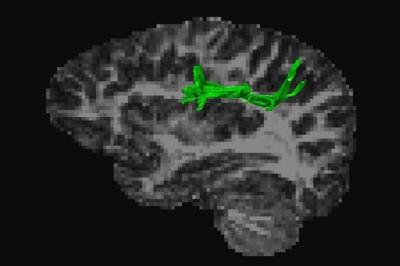

A new study led by Professor Bert De Smedt (Faculty of Psychology and Educational Sciences, KU Leuven) has found that healthy 12-year-olds who score well in addition and multiplication have higher-quality white matter tracts. This correlation does not appear to apply to subtraction and division.

In this study, the researchers had 25 children solve a series of different arithmetic operations while undergoing a brain scan. They then compared the quality of the children's white matter tracts with their arithmetic test performance.

"We found that a better quality of the arcuate fasciculus anterior – a white matter tract that connects brain regions often used for arithmetic – corresponds to better performance in adding and multiplying, while there is no correlation for subtracting and dividing."

"A possible explanation for this is that this white matter bundle is involved in rote memorization, whereas when we subtract and divide, such memorization plays less of a role. When subtracting and dividing we are more likely to use intermediary steps to calculate the solution, even as adults."